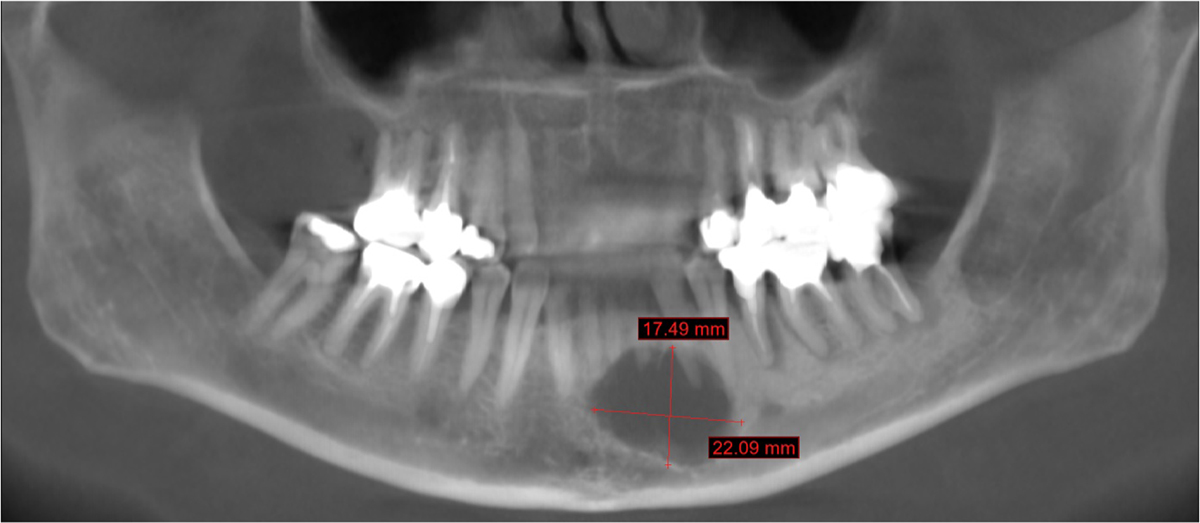

Orthopantomogram with 22 × 17 mm well-defined radiolucent lesion, anterior from mental foramina, and associated with dental root resorption.